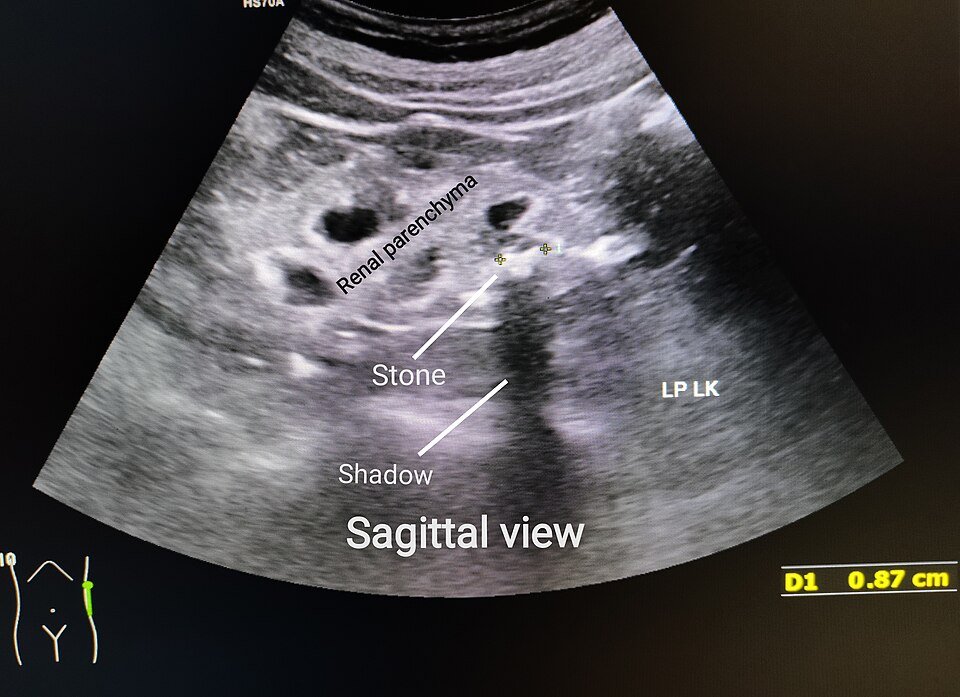

УЗИ почки: камень и риск на диете карнивор — nicetry.blog

Камни в почках после диеты. (Cerevisae, Ultrasound of left kidney lower pole with stone, Wikimedia Commons, CC BY-SA 4.0.)

Камни в почках. В 2025 American Journal of Clinical Nutrition описал клинический случай: на карнивор-рационе лабораторно выявлена высокая склонность к образованию трёх типов камней (оксалат кальция, фосфат кальция, мочевая кислота); после отказа от диеты риски снизились.

• Камни в почках. Высокий животный белок и отсутствие баланса (кальций/калий/цитрат, pH мочи) повышают литогенность мочи.